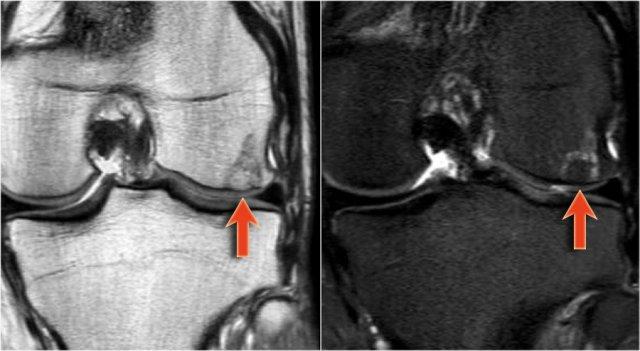

Đây là một ví dụ về sự tiến triển của u xương sụn thành u sụn ác tính ngoại vi.

Chuyển dạng ác tính

Các đặc điểm hình ảnh học cần gợi lên nghi ngờ chuyển dạng ác tính trên phim X-quang thường hoặc CT bao gồm:

- Growth of osteochondroma in skeletally mature patient

- Irregular or indistinct surface of lesions

- focal lucent regions in interior of lesions

- ăn mòn hoặc phá hủy xương lân cận

- sự hiện diện của khối mô mềm với các vôi hóa rải rác hoặc không đều